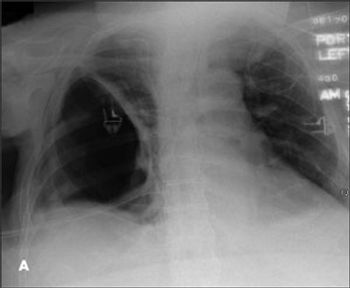

For 3 months, a 63-year-old man had experienced progressively worsening dyspnea. He denied fever, weight loss, and hemoptysis. Eight months earlier, he had had a right thoracotomy to drain a right empyema. Comorbidities included morbid obesity, type 2 diabetes mellitus, hypertension, and obstructive sleep apnea. However, he did not have any intrinsic lung disease.